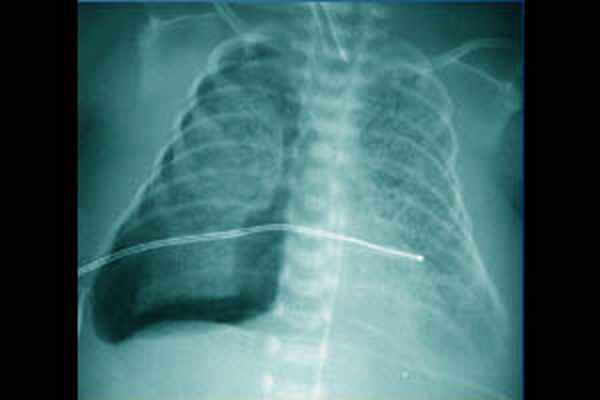

- Рентгенография ОГК. На рентгенограмме неонатолог обнаруживает просветление по периферическим отделам грудной клетки и спадение (коллапс) легкого. При этом средостение, как правило, смещено в здоровую сторону. Рентгенологическое исследование также применяется для диагностики пневмоперикарда.

У недоношенных новорожденных врачи иногда подсвечивают пораженную сторону грудной клетки с помощью светильника со световодом в затемненной комнате (трансиллюминация). Эта процедура используется для выявления свободного воздуха в окружающей легкие полости (плевральная полость). Диагноз пневмоторакса у новорожденного подтверждается рентгенологическим исследованием органов грудной клетки.

Клиническая картина напряженного пневмоторакса: тахипноэ, цианоз, втяжение уступчивых мест грудной клетки, десинхронизация с аппаратом ИВЛ, артериальная гипотензия, нарушение сердечного ритма, выраженная асимметрия грудной клетки (выбухание на стороне поражения), ослабление дыхания, коробочный перкуторный звук, перкуторные и аускультативные признаки смещения средостения в здоровую сторону, вздутие живота. Диагноз основывается на клинических данных, рентгенологическом обследовании, результате диагностической плевральной пункции, данных трансиллюминации. Последний метод требует строгих условий выполнения: относительно затемненная комната или возможность создать локальное затемнение и яркий источник холодного света малого диаметра (сильный фонарик, веновизор, светопроводник от эндоскопа). Источник света прикладывают к грудной клетке ребенка: если в плевральной полости воздуха нет, то свет будет образовывать небольшое кольцо вокруг источника света; в случае внелегочного скопления воздуха будет широкое распространение света по грудной клетке. В случае развития явной клинической картины напряженного пневмоторакса, не следует терять время на проведения дополнительного обследования, а срочно провести декомпрессию легкого. Процедура выполняется в стерильных условиях. Положение ребенка на спине. При использовании бокового доступа необходимо фиксировать руку на стороне поражения за головой. Место пункции: IV-V межреберье по переднеаксиллярной линии, по верхнему краю нижележащего ребра. Анатомическим ориентиром является сосок, располагающийся на уровне IV межреберья. Для пункции используют иглу (18G), катетер — «бабочку» (18G) или сосудистый катетер на игле (20–18G). Для дренирования с помощью торакоцентеза используются дренажные трубки 8–10 Fr или торакальные канюли 10–12 Fr. Иглу или катетер соединяют со шприцем посредством переходника с зажимом (3-ходового крана). Иглу (катетер) медленно продвигается под углом 45° в краниальном направлении, подтягивая поршень шприца на себя. При свободном поступлении воздуха в шприц воздух удаляется из плевральной полости. В случае пункции сосудистым катетером, катетер продвигается по игле на необходимую глубину, игла удаляется, и канюля соединяется с трубкой системы аспирации. Катетер фиксируется к коже. Глубина введения дренажной трубки или катетера 2–4 см в зависимости от массы тела. Дренаж фиксируют с помощью лейкопластыря, при проведении торакоцентеза — трубка закрепляется 1–2 швами. Контролируют положение дренажа рентгенологически, при наличии остаточного воздуха изменяют положение дренажа или ставят второй. Рентгенологический контроль состояния лёгких и положения дренажа после стабилизации пациента осуществляют не реже одного раза в сутки. Если лёгкие расправились и дренаж не функционирует в течение 12 ч, то его следует пережать. Если еще через 12 ч на рентгенограмме лёгкое расправлено и воздуха в плевральной полости нет, дренаж удаляют. Манипуляция проводится под местной или общей анестезией.